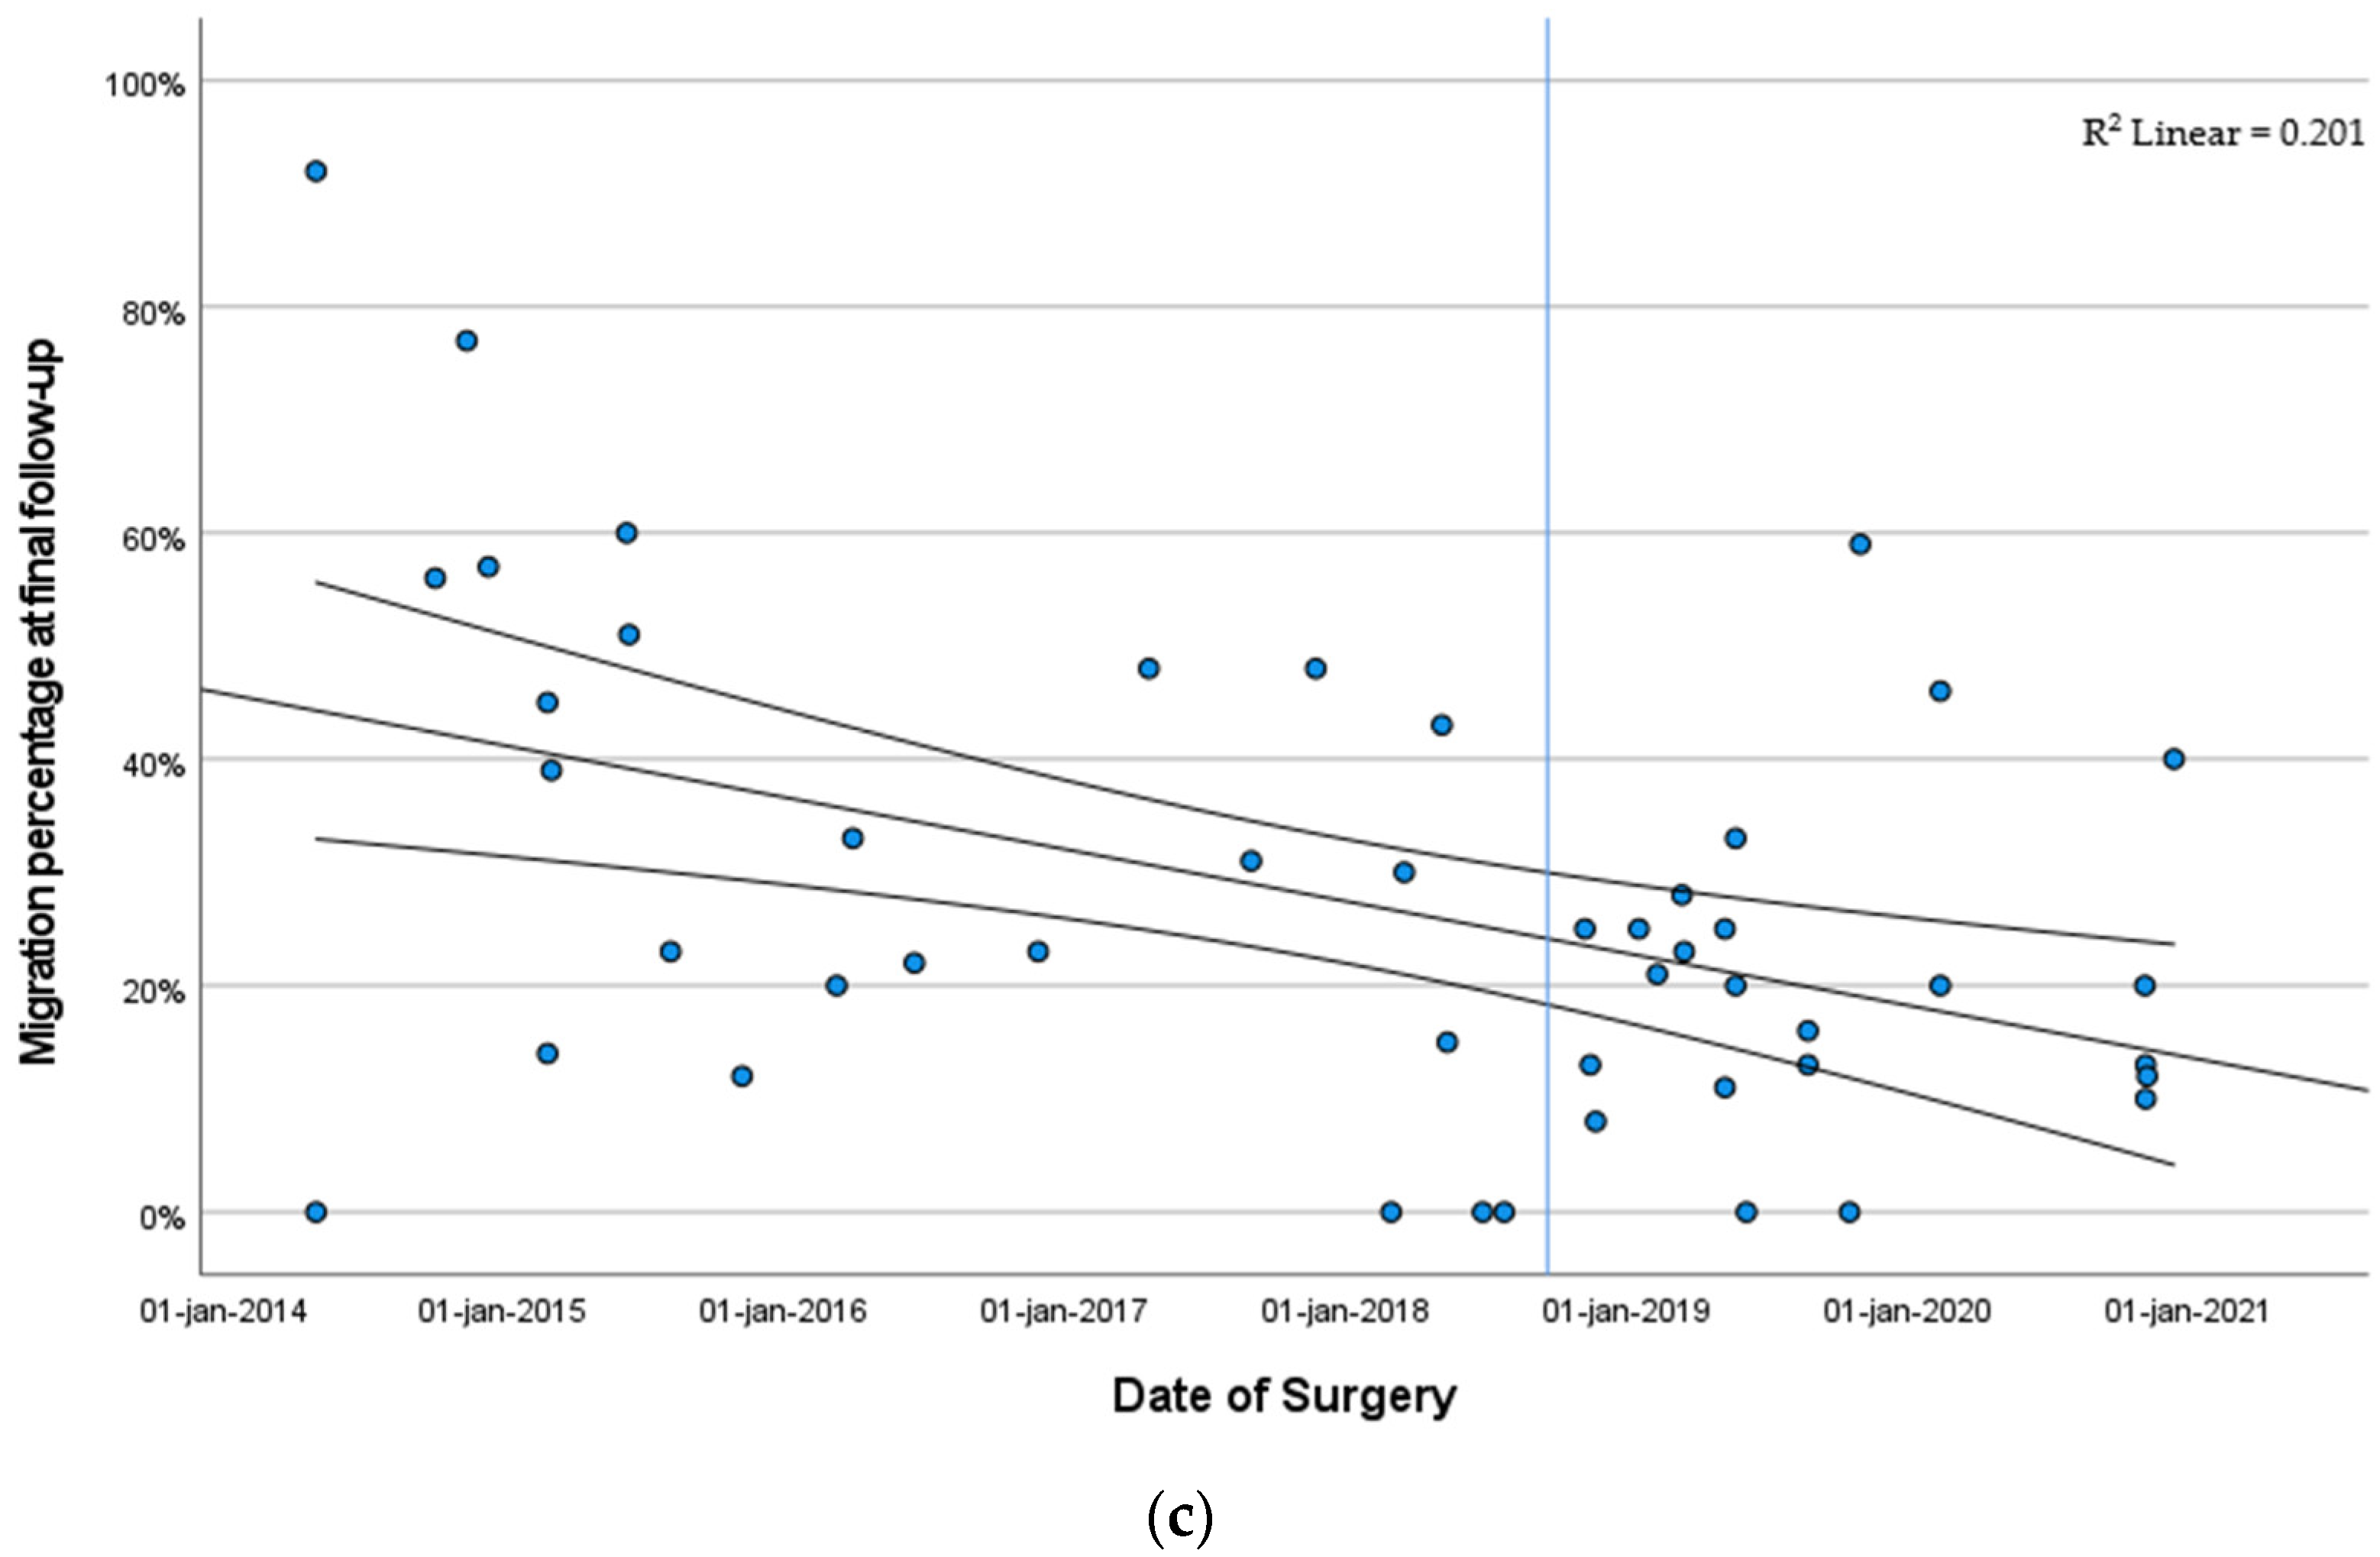

3.3. Hip Development

3.3.2. Migration Percentage Stratified by Year of Surgery

4. Discussion

5. Conclusions